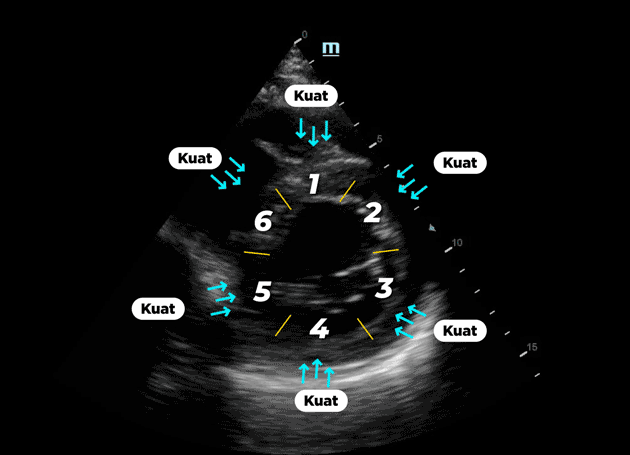

Lalu apa yang terjadi setelah 1 bulan pengobatan rutin??

Ini hasil pemeriksaan echonya :

Tampak tanda panah pada bagian 1, 5 dan 6 yang semula mengalami kelemahan, berhasil menjadi normal kembali. Seluruh bagian jantung dapat berkontraksi dengan baik. Hal ini menandakan bahwa telah terjadi perbaikan mikrosirkulasi yang luar biasa pada seluruh bagian jantung.

Yang awalnya terdapat 3 segment dari 6 segment yang mengalami kelemahan.. kini seluruh 6 segment dapat berkontraksi dengan kuat.

Selain itu, pompa jantungnya juga mengalami kenaikan. Nilai Ejection Fractional yang semula 31,86 % naik menjadi 72,14% hanya dalam waktu 1 bulan